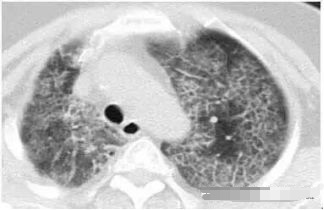

请问王大夫,这个那么像磨砂玻璃,这种是肺癌吗?

不是的,这个是肺泡蛋白沉积症,患者的肺像铺路石一样。